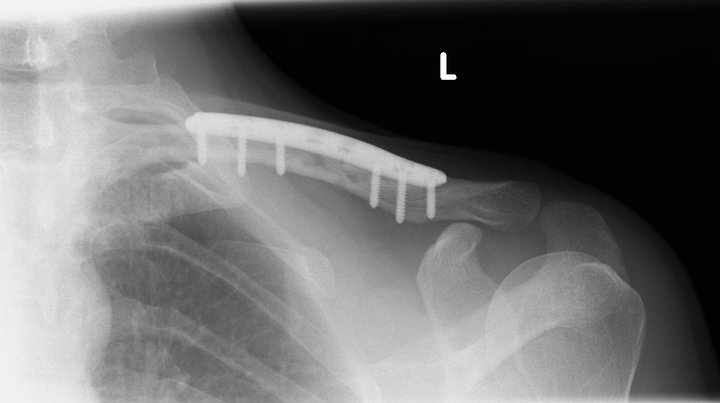

Bloody hell mate. You made a mess of that.

And I thought my right heel pain was bad.

Your photo has stopped me moaning though.

Also looks like the surgeon has raided my toolbox for screws and my posidrive screwdriver.

I think the surgeon had trouble finding the correct length screws and grabbed what ever he had.

Longer screws might work well with the shelf.

But I do have a titanium plate in my shoulder and it seems to be the norm that they just pick out the longest screws in the box